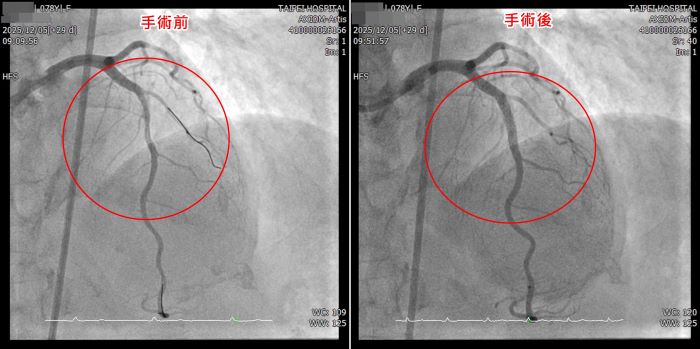

例如;臺北醫院使用血管內震波碎石術,已成功協助多位高風險病人完成困難治療。近期一名年近80歲的病人因胸口不適,檢查發現左前降支的前中段約有80%以上的狹窄病灶,且血管壁存在嚴重鈣化,最狹窄處呈現雙側鈣化,高度疑似環狀型鈣化病灶,屬於傳統氣球擴張成功率低、且血管傷害風險極高的困難病灶。

經醫療團隊與病人及家屬充分說明後,採用血管內震波碎石術,透過高能量震波選擇性擊碎血管壁內鈣化沉積,使血管恢復柔韌度,進而順利完成血管擴張與支架置放,成功完成複雜性的冠狀動脈介入手術,手術過程順利,病人術後恢復情況良好,胸口不適症狀亦獲得明顯改善。